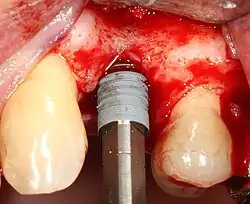

Область с единственным отсутствующим зубом

Через десну делается разрез, и лоскут ткани откидывается, чтобы показать кость челюсти.

Как только кость обнажена, серия упражнений создаёт и постепенно увеличивает участок (называемый остеотомией) для установки имплантата.

Крепление имплантата превращается в остеотомию. В идеале он полностью покрыт костью и не имеет движения внутри кости.

Формирователь десны (опора для заживления) прикрепляется к креплению имплантата, а лоскут десны накладывается на заживляющий абатмент.